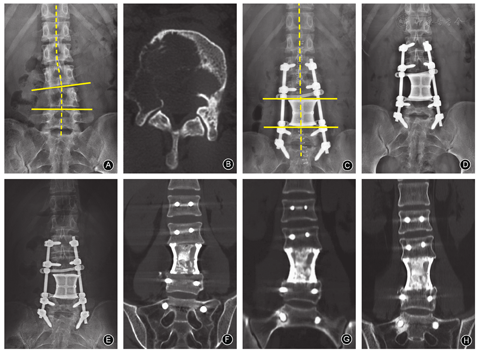

至末次随访期,15例的脊柱X线片示3D打印人工椎体与相邻上、下椎体匹配良好,固定确实,无松动、下沉及移位,未出现螺钉移位、断钉、断棒,内固定失败情况。同时3D打印人工椎体对脊柱生理曲度恢复情况良好,并且随着时间推移恢复的生理曲度并没有发生丢失(图2C,图2D, 图2E)。

通过使用个体化、功能化的3D打印人工椎体对脊柱进行重建,术后即刻X线片示3D打印人工椎体与邻近椎体上下终板接触紧密,位置良好,准确的恢复了脊柱的连续性,实现了脊柱肿瘤TES术后脊柱即刻的稳定性。同时患者VAS疼痛评分明显下降,术后(1.6±0.6)分及末次随访(1.0±0.5)分较术前(4.7±1.1)分患者疼痛明显改善。Frankle分级C级的3例术后7 d恢复到D级,末次随访时,除2例死亡,余患者Frankel分级无明显变化,取得了预期的治疗效果。在术后3个月时,人工椎体与临近椎体已有初步的骨愈合,体现了人工椎体良好的生物相容性;术后12个月时人工椎体与邻近椎体大量骨性连接形成,发生骨整合,表明人工椎体可以达到椎体间融合的要求,最终实现脊柱前柱的融合。多孔结构的构型有利于骨的长入[17]。本研究中使用的3D打印人工椎体,其自身具有多孔结构,孔径600~800 μm、孔隙率70%~80%,使得人工椎体更适宜骨长入,与邻近椎体形成良好的骨接触,最终发生骨整合,真正实现了脊柱坚强的前方融合。